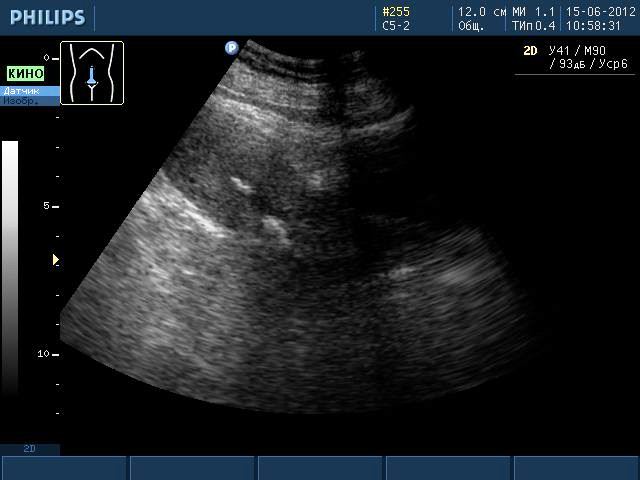

Эти образования хорошо визуализируются при проведении ультразвукового исследования или магнитно-резонансной томографии. Однако во время УЗИ невозможно увидеть ткани, из которых состоит образование, поэтому можно лишь предполагать наличие кальцината. Такая ситуация требует дополнительного обследования женщины, чтобы исключить более серьезные заболевания, чем просто наличие отложений солей кальция.

Одним из наиболее распространенных методов диагностики является ультразвуковое исследование репродуктивных органов. Гинекологи часто рекомендуют трансабдоминальное УЗИ, которое позволяет выявлять патологии органов с помощью датчиков, перемещаемых по животу пациентки.